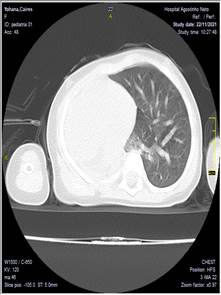

Se realizó una tomografía axial computarizada de tórax evidenciándose hipoplasia pulmonar fig. 1

Se realiza espiral tomográfico axial simple a 5 mm de tórax con reconstrucciones axiales milimétricas, sagitales y coronales en equipo multicorte observándose asimetría de ambos hemitórax, siendo mayor el derecho de aspecto compensador con desplazamiento de las estructuras del mediastino a la izquierda. Pulmón izquierdo pequeño. Presencia de disminución del calibre de los vasos pulmonares, así como el aparato bronquial.

Conclusión. Hipoplasia pulmonar izquierda

Fig. 1. Tomografía axial de tórax. A. corte axial. B. corte coronal. C. corte sagital

Tomografía de tórax: Opacidad homogénea en hemitórax izquierdo con desplazamiento de las estructuras del mediastino, reducción del volumen pulmonar derecho.